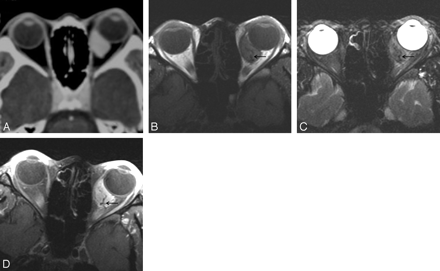

A–D, Case 5. Solitary fibrous tumor of the orbit in a 24-year-old woman. Postcontrast (A) axial CT scan and axial T1-weighted (B), T2-weighted (C), and postcontrast fat-suppressed T1-weighted (D) MR images show a 18-mm well-defined ovoid soft tissue mass in the inferomedial aspect of the intraconal space of the left orbit. Like the tumor shown in Fig 1, the mass conforms to the ocular contour without causing significant indentation. Compared with the cerebral gray matter, the mass is slightly hyperattenuated on precontrast CT scan (not shown), isointense on T1-weighted MR image (B), and mixed isointense and hyperintense and T2-weighted MR image (C). There is marked homogeneous enhancement of the tumor on postcontrast CT (A) and MR (D) images. Note the signal intensity void, tubular vascular structures inside the tumor on MR images (arrows).

The CT and MR imaging features of 6 patients with orbital SFT are summarized in the Table. All lesions were found as a solitary, well-defined, ovoid mass, ranging in size from 18 to 30 mm (mean, 24 mm). Three lesions were located in the postseptal orbit (Figs 1, 2), 2 in the lacrimal sac, and 1 on the lower eyelid (Fig 3). Although 2 of the 3 postseptal orbital lesions were found in the extraconal space at the superolateral (Fig 1) and superomedial aspect of the orbit, respectively, the remaining lesion was located in the intraconal space at the inferomedial aspect of the orbit (Fig 2). Although the eyeball was displaced by the lesion in all 3 cases, true indentation of the eyeball by the lesion was demonstrated in only 1 case. In no case was there a significant change of the bony orbit. In both lesions of the lacrimal sac, CT also showed smooth expansion of the proximal nasolacrimal duct by the inferior growth of the tumor. Compared with the cerebral cortex, the attenuation of the lesion seen on precontrast CT scans obtained in 5 patients was isoattenuated in 3 and slightly hyperattenuated in 2 (Fig 1A). There was no evidence of intralesional calcification demonstrated on precontrast CT scans. Compared with the cerebral cortex, all 3 lesions examined by MR imaging showed homogeneous isointense signal intensity on T1-weighted images (Figs 1F, 2B) and heterogeneous mixed isointense and hyperintense signal intensity on T2-weighted images (Figs 1G, 2C). In 1 of 3 lesions, signal-intensity void, tubular structures representing fast-flow vessels were found on T2-weighted and postcontrast T1-weighted MR images (Fig 2C–D).

Although not pathognomonic, homogeneous or heterogeneous-attenuated enhancement is reported to be the most prominent feature of SFT revealed with CT and MR imaging, which is attributed to high vascularity because of the prominent vascular channels within the tumor.5,16,21,23–25,27 In a likewise fashion, all 6 lesions in this study showed marked enhancement on postcontrast CT and MR images either homogeneously or heterogeneously. It is interesting to note that 1 of 3 lesions showed signal intensity-void, tubular structures on MR images (Fig 2B–D), which had not been reported by other investigators before. We believe that those structures represent fast-flow vessels within the tumor.